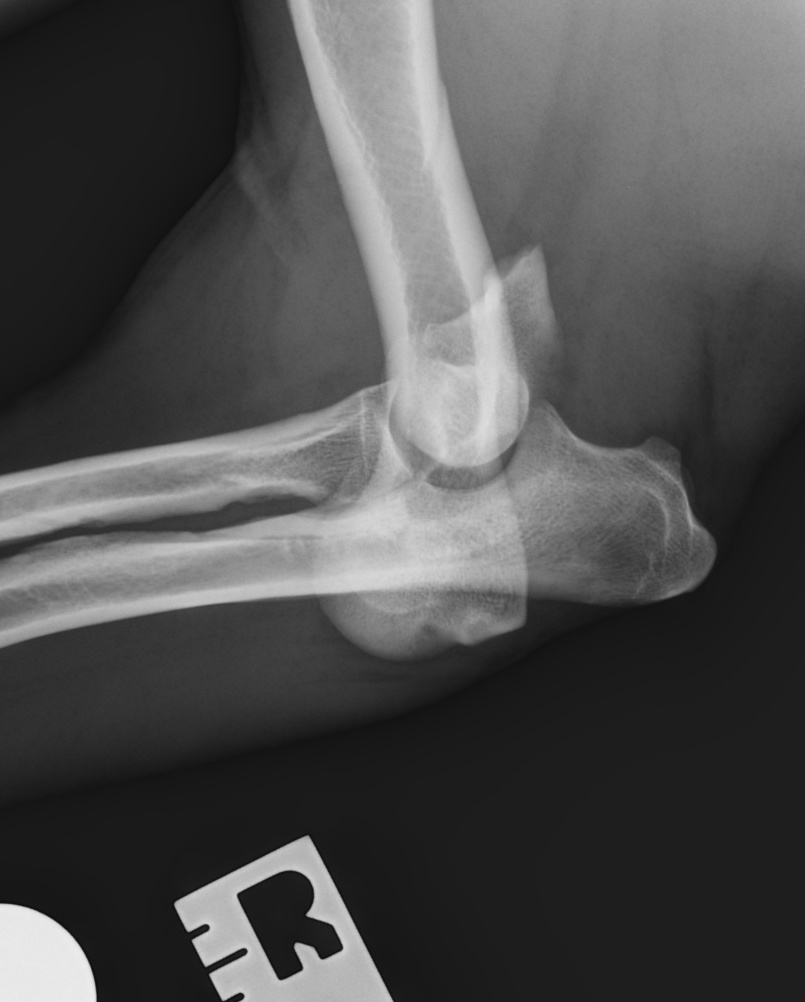

Humeral condylar fractures are a common sort of broken bone that effects the elbow in the front leg of dogs and cats. They most commonly occur in puppies between 12 and 16 weeks of age. Sometimes they occur in younger animals, and in adults they are most commonly seen in Spaniels as a consequence of humeral intracondylar fissure (HIF). They are articular fractures, which means that they involve the joint surface and should be treated promptly with surgical fixation.

Effected dogs suddenly become very lame on the leg, and might stop using it altogether. However, the lameness can improve quite quickly in some dogs, and these fractures occasionally go undiagnosed for some days or even weeks. This can make them very difficult to repair, as bone heals quickly in puppies. But the elbow joint is left in a very abnormal shape if they heal in the wrong place, and long-term function can be poor if they are not treated surgically.

Radiographs (x-rays) are usually enough to make a diagnosis and plan surgery. However, especially in adult dogs, a CT scan is a good idea to check the other elbow for signs of HIF.

- How many pieces the bone is broken into. Usually, just one side of the humerus fractures off, and these fractures are more straightforward to stabilise and generally have better outcomes. Approximately 35% of condylar fractures are Y-fractures, where both sides of the humeral condyle break apart from each other and from the main shaft of the bone. These are much more difficult to stabilise.